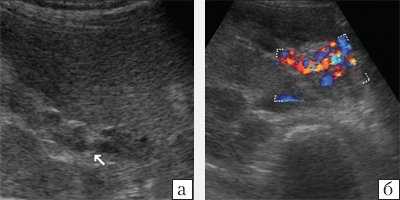

При ультразвуковом исследовании (УЗИ) в серошкальном режиме в просвете воротной вены можно выявить неоднородное образование повышенной или смешанной эхогенности, с неровными, нечеткими контурами, препятствующее кровотоку, размеры которого могут быть различными: от 0,5 см до полной окклюзии воротной вены и/или ее ветвей (рис. 1, а). Эхогенность тромба чаще является более высокой, чем окружающей его крови. Однако на ранних стадиях формирования эхогенность может отличаться настолько незначительно, что визуализация тромба чрезвычайно сложна. Могут определяться увеличение диаметра сосуда с нечеткостью контуров, увеличение печени и снижение ее эхогенности, увеличение селезенки. Могут быть найдены первопричины тромбоза воротной вены: гепатоцеллюлярная карцинома, метастазы, цирроз печени, новообразования поджелудочной железы и др. При пилефлебите обнаруживают абсцессы печени [3].

a) В-режим. Неоднородное образование повышенной эхогенности с неровными, нечеткими контурами в просвете воротной вены (стрелки).

б) Режим ЦДК. Полное отсутствие допплеровских сигналов внутри просвета сосуда; допплеровский сигнал определяется в сети мелких коллатералей.

При ЦДК отмечается полное или частичное отсутствие допплеровских сигналов внутри просвета сосуда; в случае частичного тромбоза сигнал определяется пристеночно вокруг тромба, частично окклюзирующего вену, либо в сети узких коллатералей (рис. 1, б). В случае частичного тромбоза определяется допплеровский сигнал с признаками турбулентности на фоне повышенной скорости кровотока. При опухолевом тромбозе кровоток может быть пульсирующим либо непрерывным [2, 3]. Визуализируются мелкие или крупные коллатерали. При кавернозной трансформации воротной вены в режиме ЦДК в коллатералях определяется сглаженная допплеровская кривая со средней скоростью кровотока меньше 8 см/с [5]. Возможны кавернозные мальформации вены, спонтанные порто-портальные, порто-кавальные и спленоренальные шунты.